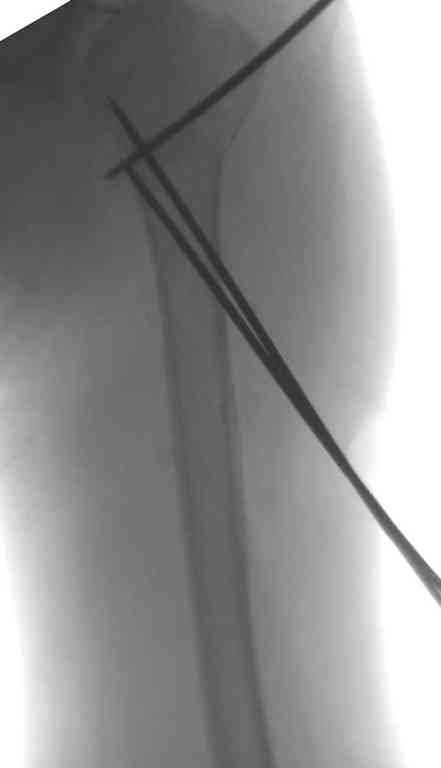

Неплохой бюджетный и косметический вариант, хотя в руках автора это это очень просто, а у нас приходилось "посветиться ", репозицию проводили

короткими 2 мм спицами -джойстиками,их же использовали для временной фиксации (а в некоторых случаях и для окончательной), варинат фиксация

TENами.

Неправильно выбранная тактика по фиксации или технические ошибки во время операции могут привести к серьезным осложнениям. Здесь привожу

пример из нашей практики, вроде обычный перелом шейки, фиксированный популярным методом "Сиэтла" - множественными спицами 2.8 мм с резьбой на конце.

При первичном осмотре в поликлинике через 3 недели обнаружили миграцию двух спиц, срочно госпитализированному на второй день перед операцией на всякий случай сделали снимок, одна спица находилась под ключицей в шейном отделе (на снимке).